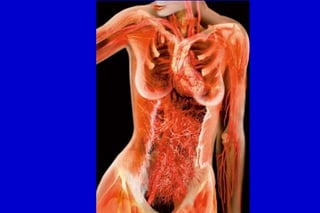

El mantenimiento de una postura normal del pié con arco

longitudinal interno depende del balance entre

articulaciones móviles, ligamentos intactos y asctividad

muscular.

Tendón del tibial posterior

Ligamento calcáneo escafoideo

Ligamento deltoideo (haz superficial)